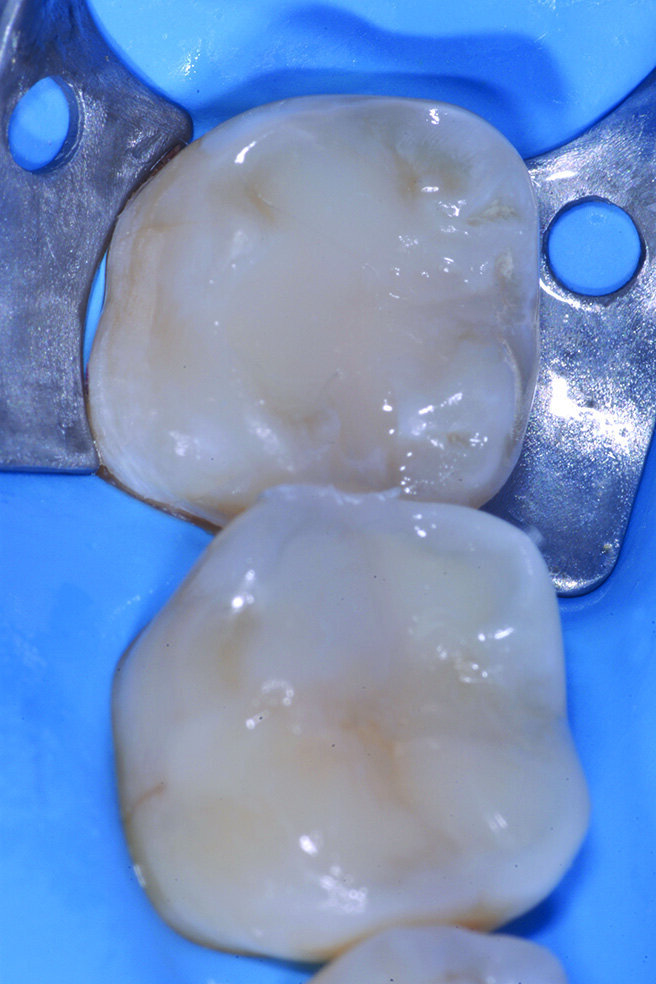

Figg. 2-5_Rimozione dei vecchi restauri presenti su 4.6 e 4.7: gli elementi vengono restaurati con tecnica diretta utilizzando dentina e smalto Enamel Plus HRI Bio Function.

Figg. 6-9_Le superfici occlusali erose e/o abrase vengono ricostruite con strati sottili di smalto composito Enamel Plus HRi Bio Function.

Per evitare preparazioni che porterebbero al sacrificio di tessuto sano si preferisce ricostruire gli elementi in modo ultraconservativo con una tecnica diretta per addizione. I restauri presenti su 4.6 e 4.7 vengono rimossi e tutte le superfici da ricostruire sabbiate con ossido di alluminio e lo smalto interessato all’adesione viene poi lucidato con un gommino in silicone prima delle fasi adesive. Le cavità su 4.6 e 4.7 vengono prima riempite con piccoli incrementi di dentina quindi tutte le superfici occlusali erose e/o abrase vengono ricostruite con strati sottili di smalto composito (Enamel Plus HRi Bio Function).